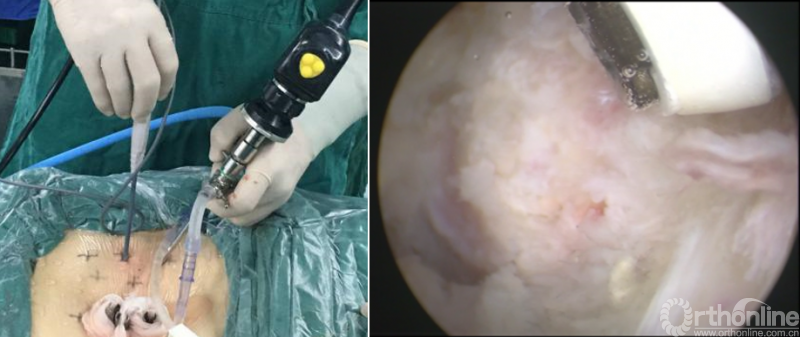

BELIF技术十步法

详细步骤:一定、二剥、三凿、四分、五咬、六切、七牵、八铰、九填、十置

第六步“切”:切除椎间盘;

第七步“牵”:神经拉钩牵拉保护神经根;

第八步“铰”:铰刀置入处理上下终板(刮勺置入处理终板);

第九步“填”:椎间隙填塞植骨;

第十步“置”:置入融合器、经皮钉。